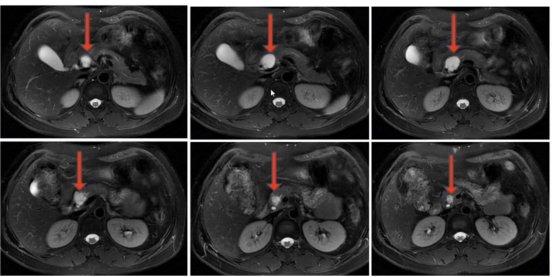

該患者體檢時(shí)發(fā)現(xiàn)胰腺囊性占位,因擔(dān)心外科手術(shù)創(chuàng)傷,遲遲未敢治療,隨著囊腫逐漸增大,出現(xiàn)了反復(fù)腹痛癥狀。來(lái)到衡陽(yáng)市中心醫(yī)院消化內(nèi)科就診后,醫(yī)生團(tuán)隊(duì)為其完善超聲內(nèi)鏡及囊液分析等檢查,明確診斷為胰腺粘液性囊腫,排除禁忌證后實(shí)施了聚桂醇滅活術(shù)。術(shù)后患者腹痛癥狀即刻緩解,住院3天便順利出院,復(fù)查時(shí)囊腫體積已明顯縮小,生活質(zhì)量完全恢復(fù)正常。

胰腺作為人體消化系統(tǒng)的“核心引擎”,深藏于腹腔深處,其病變往往隱匿難察,治療難度頗高。胰腺囊性占位是臨床常見(jiàn)的胰腺病變,涵蓋假性囊腫、囊性腫瘤等多種類型,部分病變存在癌變風(fēng)險(xiǎn),或因體積增大壓迫周圍器官引發(fā)腹痛、腹脹等不適,嚴(yán)重影響患者生活質(zhì)量。以往傳統(tǒng)治療多依賴外科手術(shù),創(chuàng)傷大、恢復(fù)慢,且可能伴隨胰漏、出血等并發(fā)癥,患者顧慮很多?,F(xiàn)在,衡陽(yáng)市中心醫(yī)院消化內(nèi)科團(tuán)隊(duì)推出超聲內(nèi)鏡(EUS)引導(dǎo)下胰腺囊性占位聚桂醇滅活術(shù),為患者帶來(lái)精準(zhǔn)、安全、高效的診療新選擇。該技術(shù)“超級(jí)微創(chuàng)”,將超聲內(nèi)鏡的“精準(zhǔn)導(dǎo)航”與聚桂醇的“溫和消融”完美結(jié)合,適用于直徑>1cm、有癥狀的胰腺囊性病變,以及高齡、合并基礎(chǔ)疾病無(wú)法耐受外科手術(shù)或拒絕手術(shù)的患者。手術(shù)全程在超聲內(nèi)鏡實(shí)時(shí)引導(dǎo)下進(jìn)行,醫(yī)生可清晰洞察病灶位置、大小及與周圍血管、器官的解剖關(guān)系,通過(guò)細(xì)針穿刺精準(zhǔn)穿刺至囊腔內(nèi),抽凈囊液后注入聚桂醇硬化劑,實(shí)現(xiàn)對(duì)病灶的靶向滅活。整個(gè)手術(shù)僅需30分鐘左右,全程微創(chuàng),無(wú)需開腹,僅留下細(xì)微穿刺痕跡,有效避免了傳統(tǒng)手術(shù)對(duì)胰腺及周圍組織的損傷,最大程度保留胰腺正常生理功能。

聚桂醇滅活術(shù)是消化介入領(lǐng)域的前沿技術(shù),憑借其安全性高、不良反應(yīng)少的優(yōu)勢(shì),逐步取代傳統(tǒng)消融劑成為囊性病變治療的優(yōu)選方案。與傳統(tǒng)無(wú)水乙醇消融相比,聚桂醇通過(guò)改變細(xì)胞膜表面能量分布,破壞囊壁內(nèi)皮細(xì)胞,引發(fā)無(wú)菌性炎癥及纖維組織增生,最終實(shí)現(xiàn)囊腔閉合,不僅消融效果確切,且術(shù)后腹痛、醉酒樣反應(yīng)等不良反應(yīng)發(fā)生率極低,總體并發(fā)癥發(fā)生率僅4.3%,顯著提升了治療的安全性與患者耐受性。臨床研究顯示,該技術(shù)總體消融有效率高達(dá)94.7%,隨訪12個(gè)月以上的長(zhǎng)期有效率亦達(dá)79.4%。